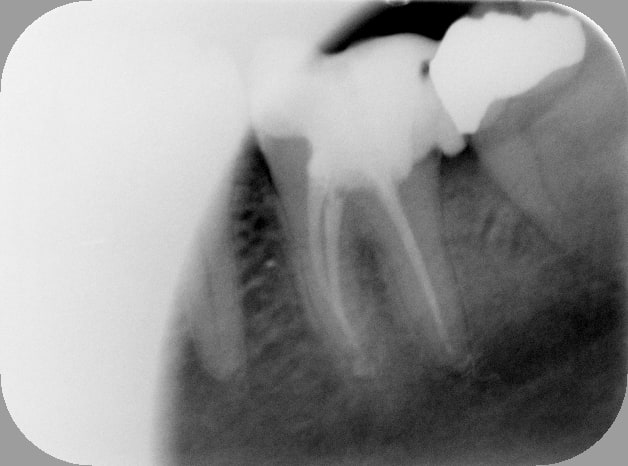

Apr s oqfrgc - Eugenol